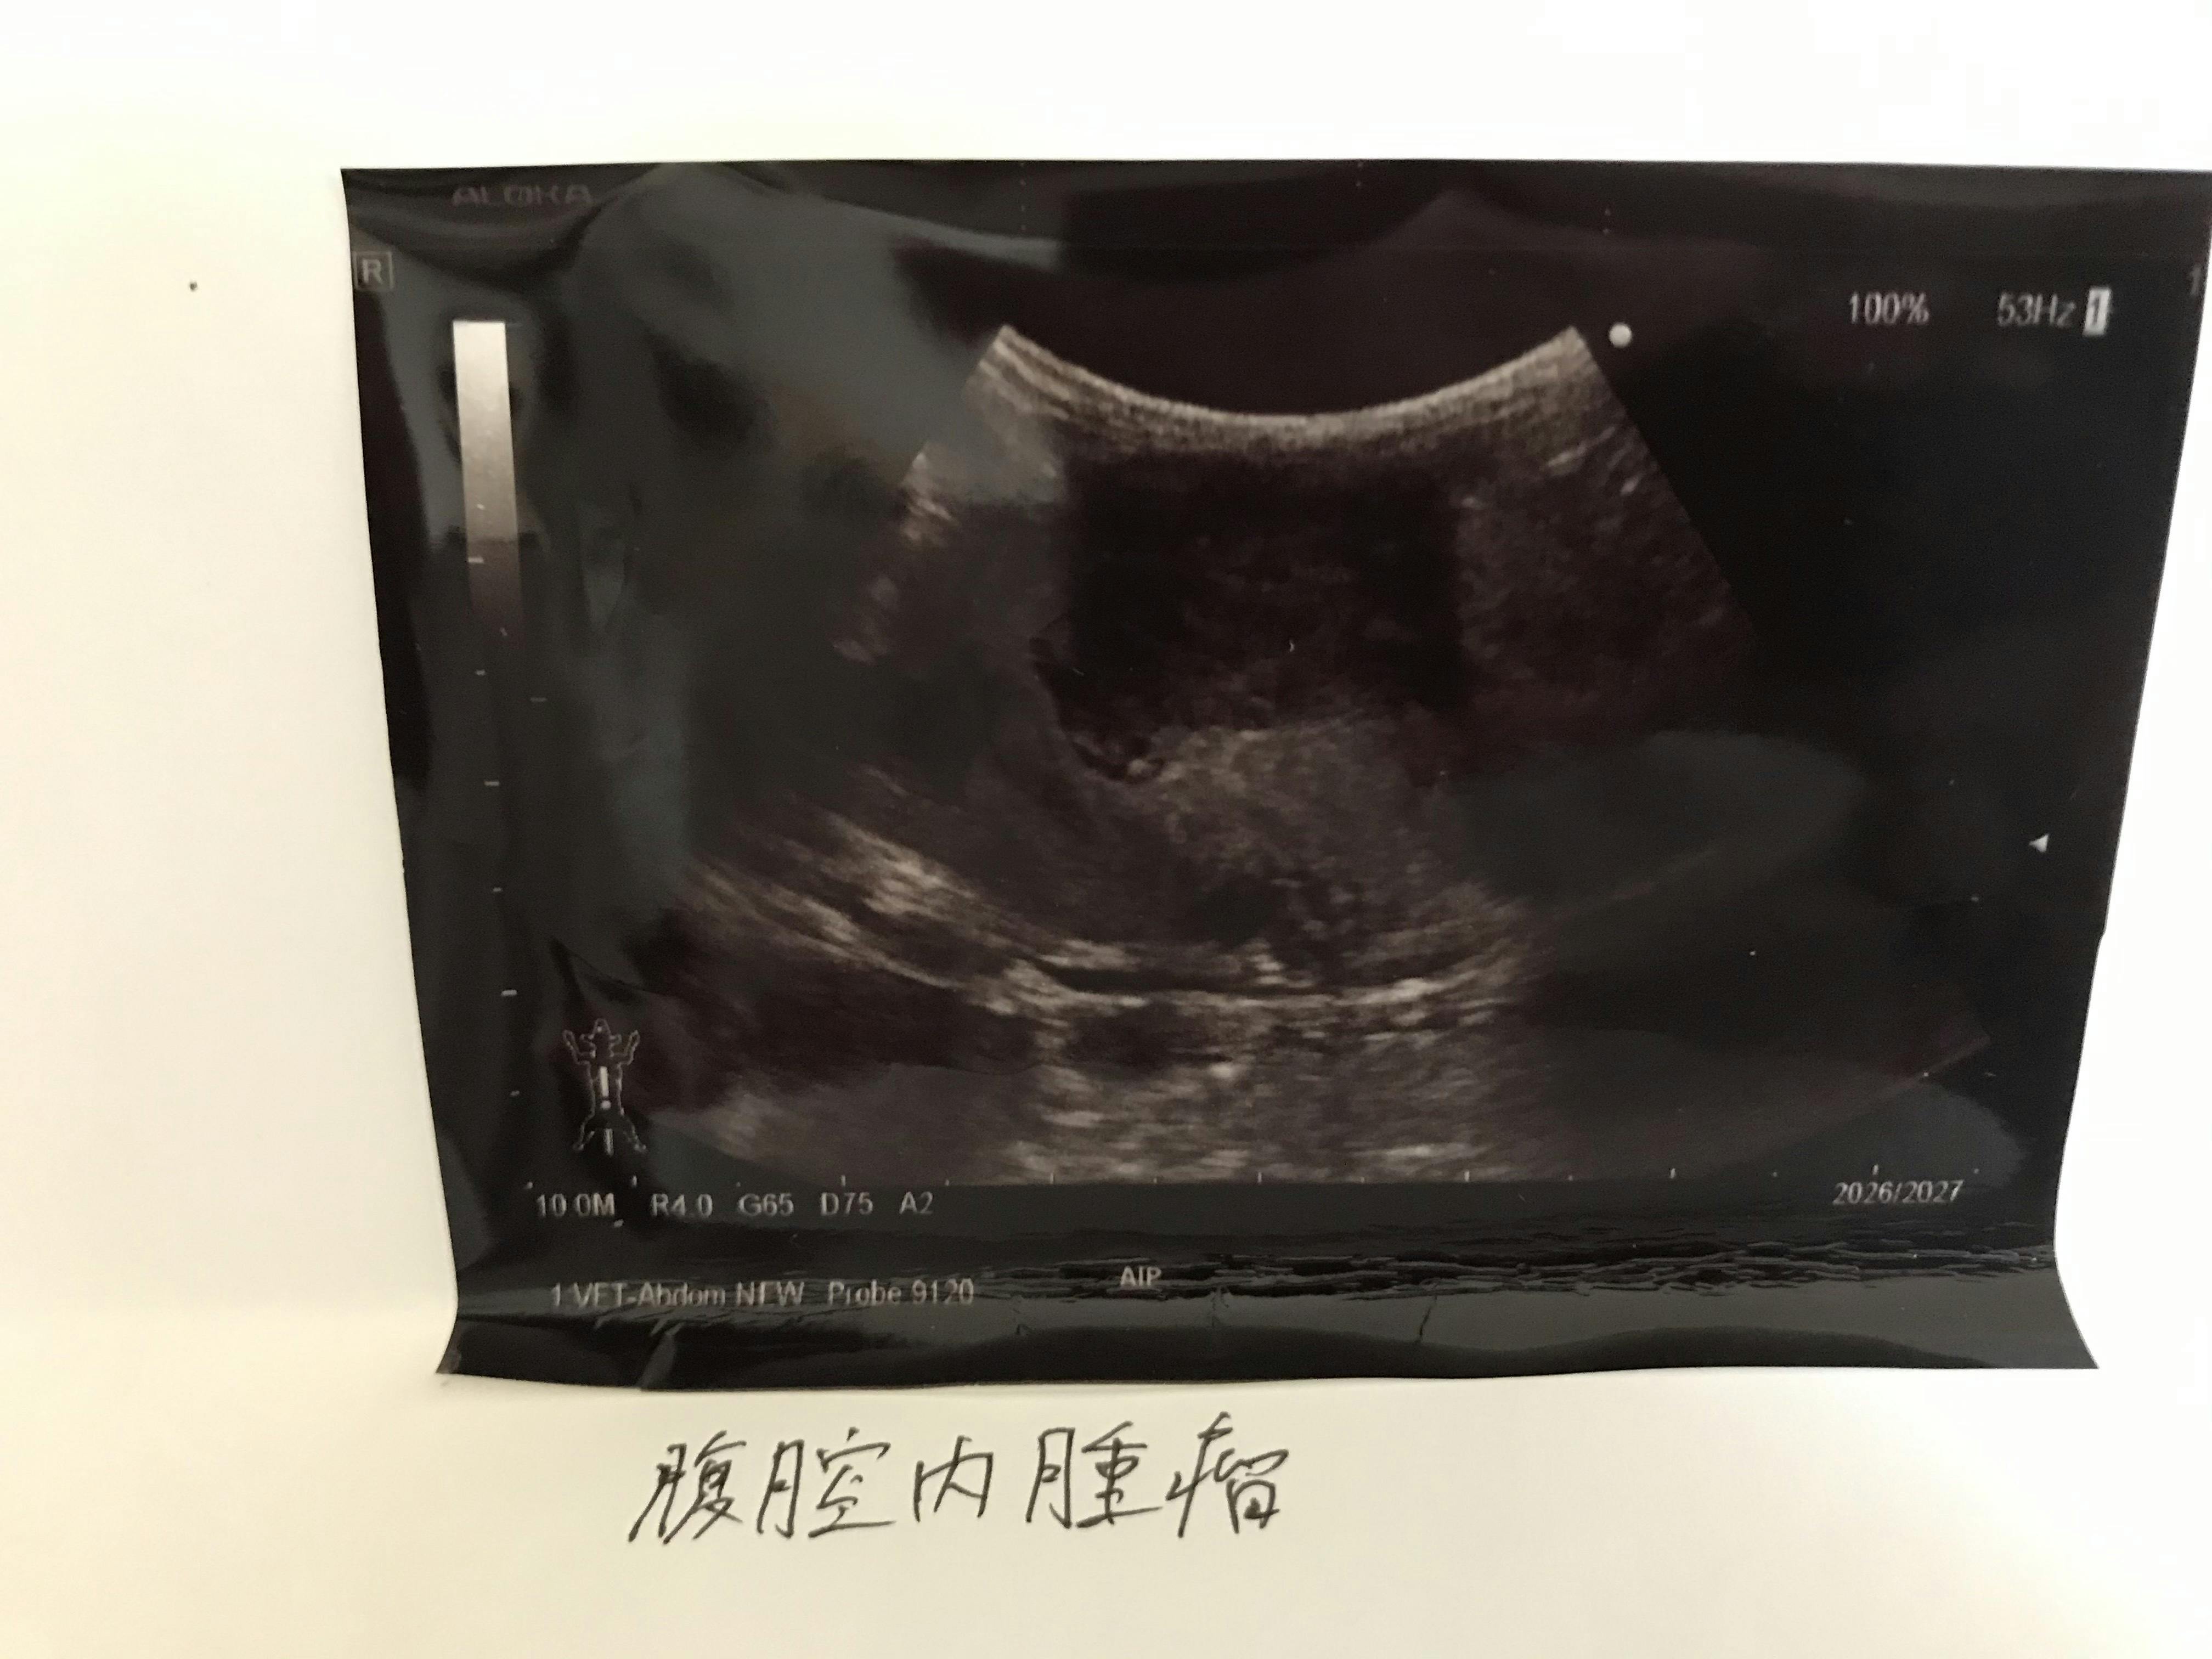

高熱があったこともあり、念のため超音波検査をしたところ、腹水が3つ見つかりました。

万が一のことを考えて血液検査も行った結果、貧血と肝臓の数値が高いことから、FIP(ウェットタイプ)の疑惑が出たため外部検査も行うことにしました。

後日、外部検査の結果 FIP(ウェットタイプ)と診断されました。